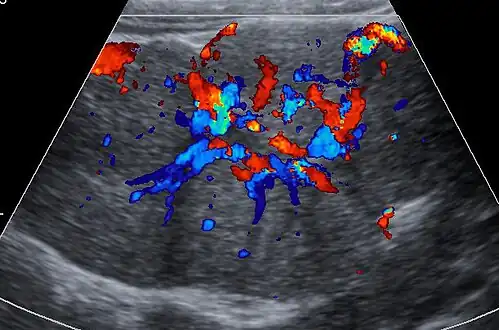

Ultrasound of malformed vessels within the fibrous scar of FNH.

Unenhanced CT or MRI usually does not show the difference in intensity between the FNH and surrounding liver except when there is marked liver steatosis that reduces the attenuation of the liver, causing FNH to be hyperattenuating when compared with the surrounding liver. In the arterial phase CT or MRI, there is a strong enhancement not followed by washout. The lesion presents a slight hyperintensity or isodensity on portal venous phase or delayed phase images. There is also a presence of a central scar and absence of a capsule for the FNH.[4]